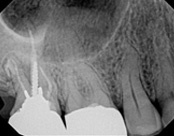

In this situation, some would say the canals are so “calcified” that root canal treatment can’t be done; or sometimes the canal can’t be found. And because of that the tooth would need an extraction and an implant. In some instances, root canal therapy can’t be done but that does not mean the tooth is a loss. The solution is micro-apical surgery, an apicoectomy.